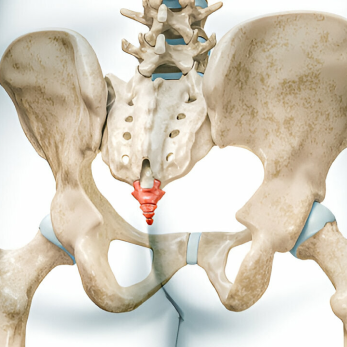

Anatomy of the Coccyx

Coccyx is the distal most part of the spine. It is triangular in shape and comprises of 3-5 fused segments. It serves as one leg of the tripod, also comprising of the two ischial tuberosities and this tripod forms the weight bearing surface in a seated position. It forms a central connecting point for various pelvic floor muscles which support the anus, vagina in females and also play a supporting role in defecation, walking and running. (Diagram to be added)

The ganglion impair is a terminal midline sympathetic ganglion which is present over the first coccygeal vertebral body and the sacrococcygeal junction. It is a very useful treatment modality as this block provides relief of coccydynia and pain involving the lower part of the rectum, anus, urethra, and vagina.